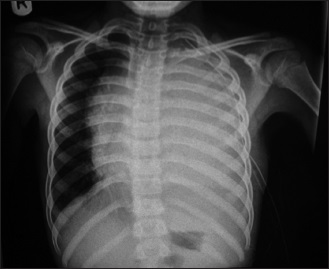

Baseline chest radiographic features among antiretroviral therapy naïve human immuno-deficiency virus positive children in a pediatric care program

Dr. Omolola M. Atalabi, Regina Oladokun, Babatunde Adedokun, Millicent O Obajimi, Kikelomo Osinusi (Author)